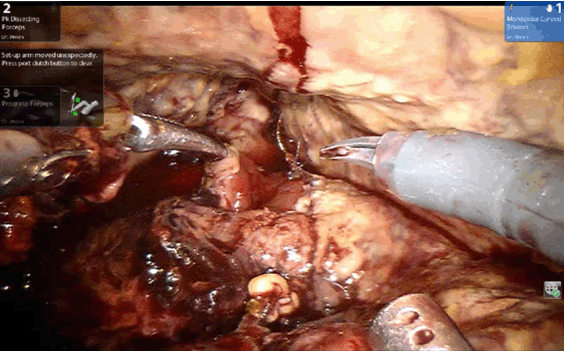

The patient was returned to operating theatre for Da Vinci Si HD (Intuitive Surgical Inc, USA) robot-assisted reconstruction of urethrovesical anastomosis. Intraoperatively, complete urethrovesical anastomosis disruption was evident (Figure 2), and there appeared to be an anastomotic suture breakage and splitting of the bladder neck. The repair process was difficult due to tissue fragility. The anastomosis was repaired with monofilament suture by van Velthoven style; reinforcements with simple interrupted suture were made at 2 o'clock, 5 o'clock, 7 o'clock and 10 o'clock. Patient recovered well postoperatively but anastomotic leak was persistent. The urinary catheter was kept in for four weeks total after which cystogram showed water-tight healing.

Figure 2: Total urethrovesical anastomotic disruption seen on robotic camera.